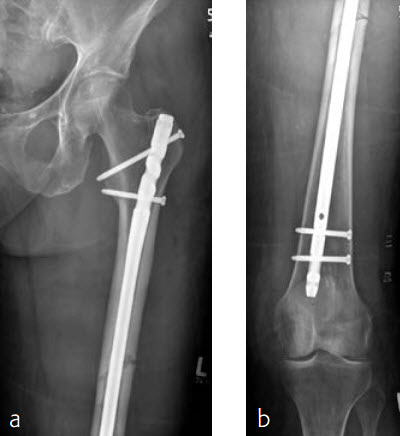

An 86-year-old patient fell at home while dressing, sustaining a subtrochanteric left femur fracture (Fig 1). The CT scan confirmed no involvement of the intertrochanteric region or the piriformis fossa. Fixation was with FRN for piriformis fossa entry point in reconstruction locking mode and transverse locking (Fig 2).